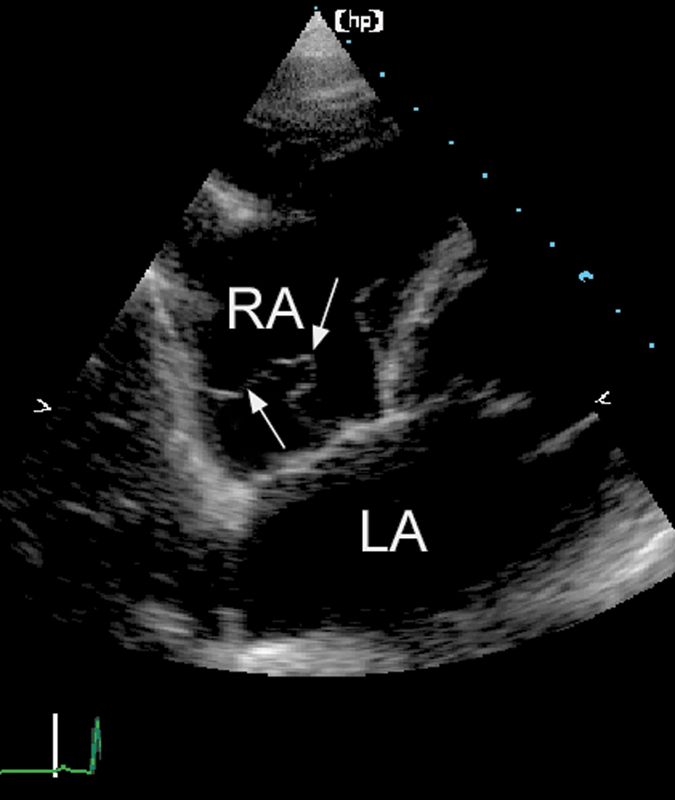

فحوصات تشخيصية لبعض امراض القلب والشرايين التاجية